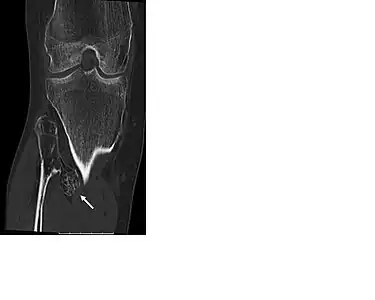

multiple osteochondromas around the knee -

CT of osteochondroma in MO